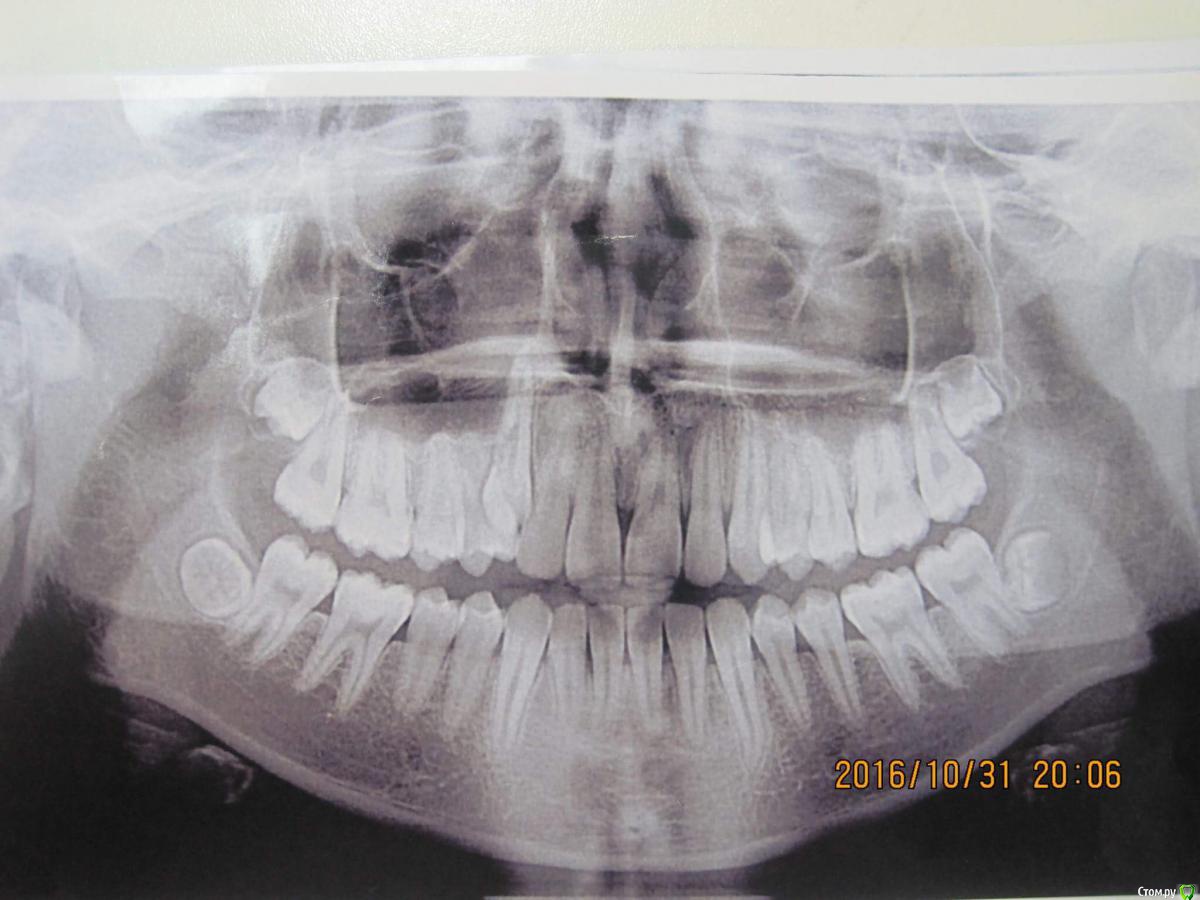

simpsons Опубликовано 8 декабря, 2016 Поделиться Опубликовано 8 декабря, 2016 Пытаемся вытянуть 13, но попытки тщетны... хочу знать мнения как поступают в таких ситуациях , если есть заместительная резорбция корня ( анкилоз)? Ссылка на комментарий

Yana guapa Опубликовано 9 декабря, 2016 Поделиться Опубликовано 9 декабря, 2016 Пытаемся вытянуть 13, но попытки тщетны... хочу знать мнения как поступают в таких ситуациях , если есть заместительная резорбция корня ( анкилоз)? 1. во-первых, хотелось бы спросить откуда такой диагноз? (Заместительная резорбция Зубоальвеолярный анкилоз может проявляться образованием костной ткани в ответ на обширный некроз периодонтальной связки. Клинически это состояние обычно является осложнением подвывихов или вывихов зубов, а особенно полных вывихов, при которых зубы находились вне полости рта достаточно длительное время, в связи с чем произошла гибель клеток периодонтальной связки и нарушение прикрепления в области корня. Если в процесс вовлекается менее 20% поверхности корня, явления анкилоза оказываются обратимыми.В противном случае зуб становится частью альвеолярной кости и включается в процесс нормальной перестройки костной ткани. Соответственно, происходит постепенная резорбция тканей зуба и замещение их костной тканью, в связи с чем процесс называют заместительной резорбцией. Остеокласты, являющиеся основными клетками, участвующими в процессе заместительной резорбции, осуществляют ремоделировку костной ткани. Клинически зубоальвеолярный анкилоз характеризуется исчезновением подвижности зуба. При перкуссии определяется специфический металлический звук, а со временем зубы оказываются в инфраокклюзии. Рентгенологически наблюдается исчезновение периодонтальной щели. Кроме того, врастание кости в ткани зуба в процессе заместительной резорбции придает зубу характерный «изъеденный» вид.) это я так, для себя. Мы об одном и том же думаем? 2. или Вы решили , что зуб анкилозирован, только из-за того, что не выходит? Я могу предположить, что у зуба есть шанс, если все сделать грамотно. - создать место-использовать удобные и быстрые дуги (типа cantilever или ballista ) 3. конечно такие кейсы нужно оформлять более информативно, если хотите получить больше советов ( фото прикуса в фас, профиль; лицо), срезы КТ http://i12.pixs.ru/thumbs/4/4/8/IMG4417JPG_3567295_24358448.jpg http://i12.pixs.ru/thumbs/4/6/0/IMG4426JPG_9513930_24358460.jpg 1 Ссылка на комментарий

Yana guapa Опубликовано 9 декабря, 2016 Поделиться Опубликовано 9 декабря, 2016 Пытаемся вытянуть 13, но попытки тщетны... хочу знать мнения как поступают в таких ситуациях , если есть заместительная резорбция корня ( анкилоз)? что со средний линией? походу именно с ней и нужно работать. Брекеты на 7ках не стоят.... Опору терять начинаете... надо ставить нормальную полноценную систему, развивать зубные арки, центровать средние линии, создавать место , тянуть и ..... конечно же молиться!)))))) 1 Ссылка на комментарий

simpsons Опубликовано 10 декабря, 2016 Автор Поделиться Опубликовано 10 декабря, 2016 1. во-первых, хотелось бы спросить откуда такой диагноз? (Заместительная резорбция Зубоальвеолярный анкилоз может проявляться образованием костной ткани в ответ на обширный некроз периодонтальной связки. Клинически это состояние обычно является осложнением подвывихов или вывихов зубов, а особенно полных вывихов, при которых зубы находились вне полости рта достаточно длительное время, в связи с чем произошла гибель клеток периодонтальной связки и нарушение прикрепления в области корня. Если в процесс вовлекается менее 20% поверхности корня, явления анкилоза оказываются обратимыми.В противном случае зуб становится частью альвеолярной кости и включается в процесс нормальной перестройки костной ткани. Соответственно, происходит постепенная резорбция тканей зуба и замещение их костной тканью, в связи с чем процесс называют заместительной резорбцией. Остеокласты, являющиеся основными клетками, участвующими в процессе заместительной резорбции, осуществляют ремоделировку костной ткани. Клинически зубоальвеолярный анкилоз характеризуется исчезновением подвижности зуба. При перкуссии определяется специфический металлический звук, а со временем зубы оказываются в инфраокклюзии. Рентгенологически наблюдается исчезновение периодонтальной щели. Кроме того, врастание кости в ткани зуба в процессе заместительной резорбции придает зубу характерный «изъеденный» вид.) это я так, для себя. Мы об одном и том же думаем? 2. или Вы решили , что зуб анкилозирован, только из-за того, что не выходит? Я могу предположить, что у зуба есть шанс, если все сделать грамотно. - создать место-использовать удобные и быстрые дуги (типа cantilever или ballista ) 3. конечно такие кейсы нужно оформлять более информативно, если хотите получить больше советов ( фото прикуса в фас, профиль; лицо), срезы КТ Спасибо. Об одном и том же. Ссылка на комментарий

simpsons Опубликовано 10 декабря, 2016 Автор Поделиться Опубликовано 10 декабря, 2016 что со средний линией? походу именно с ней и нужно работать. Брекеты на 7ках не стоят.... Опору терять начинаете... надо ставить нормальную полноценную систему, развивать зубные арки, центровать средние линии, создавать место , тянуть и ..... конечно же молиться!)))))) Центральная линия смещена. Спасибо!) Ссылка на комментарий